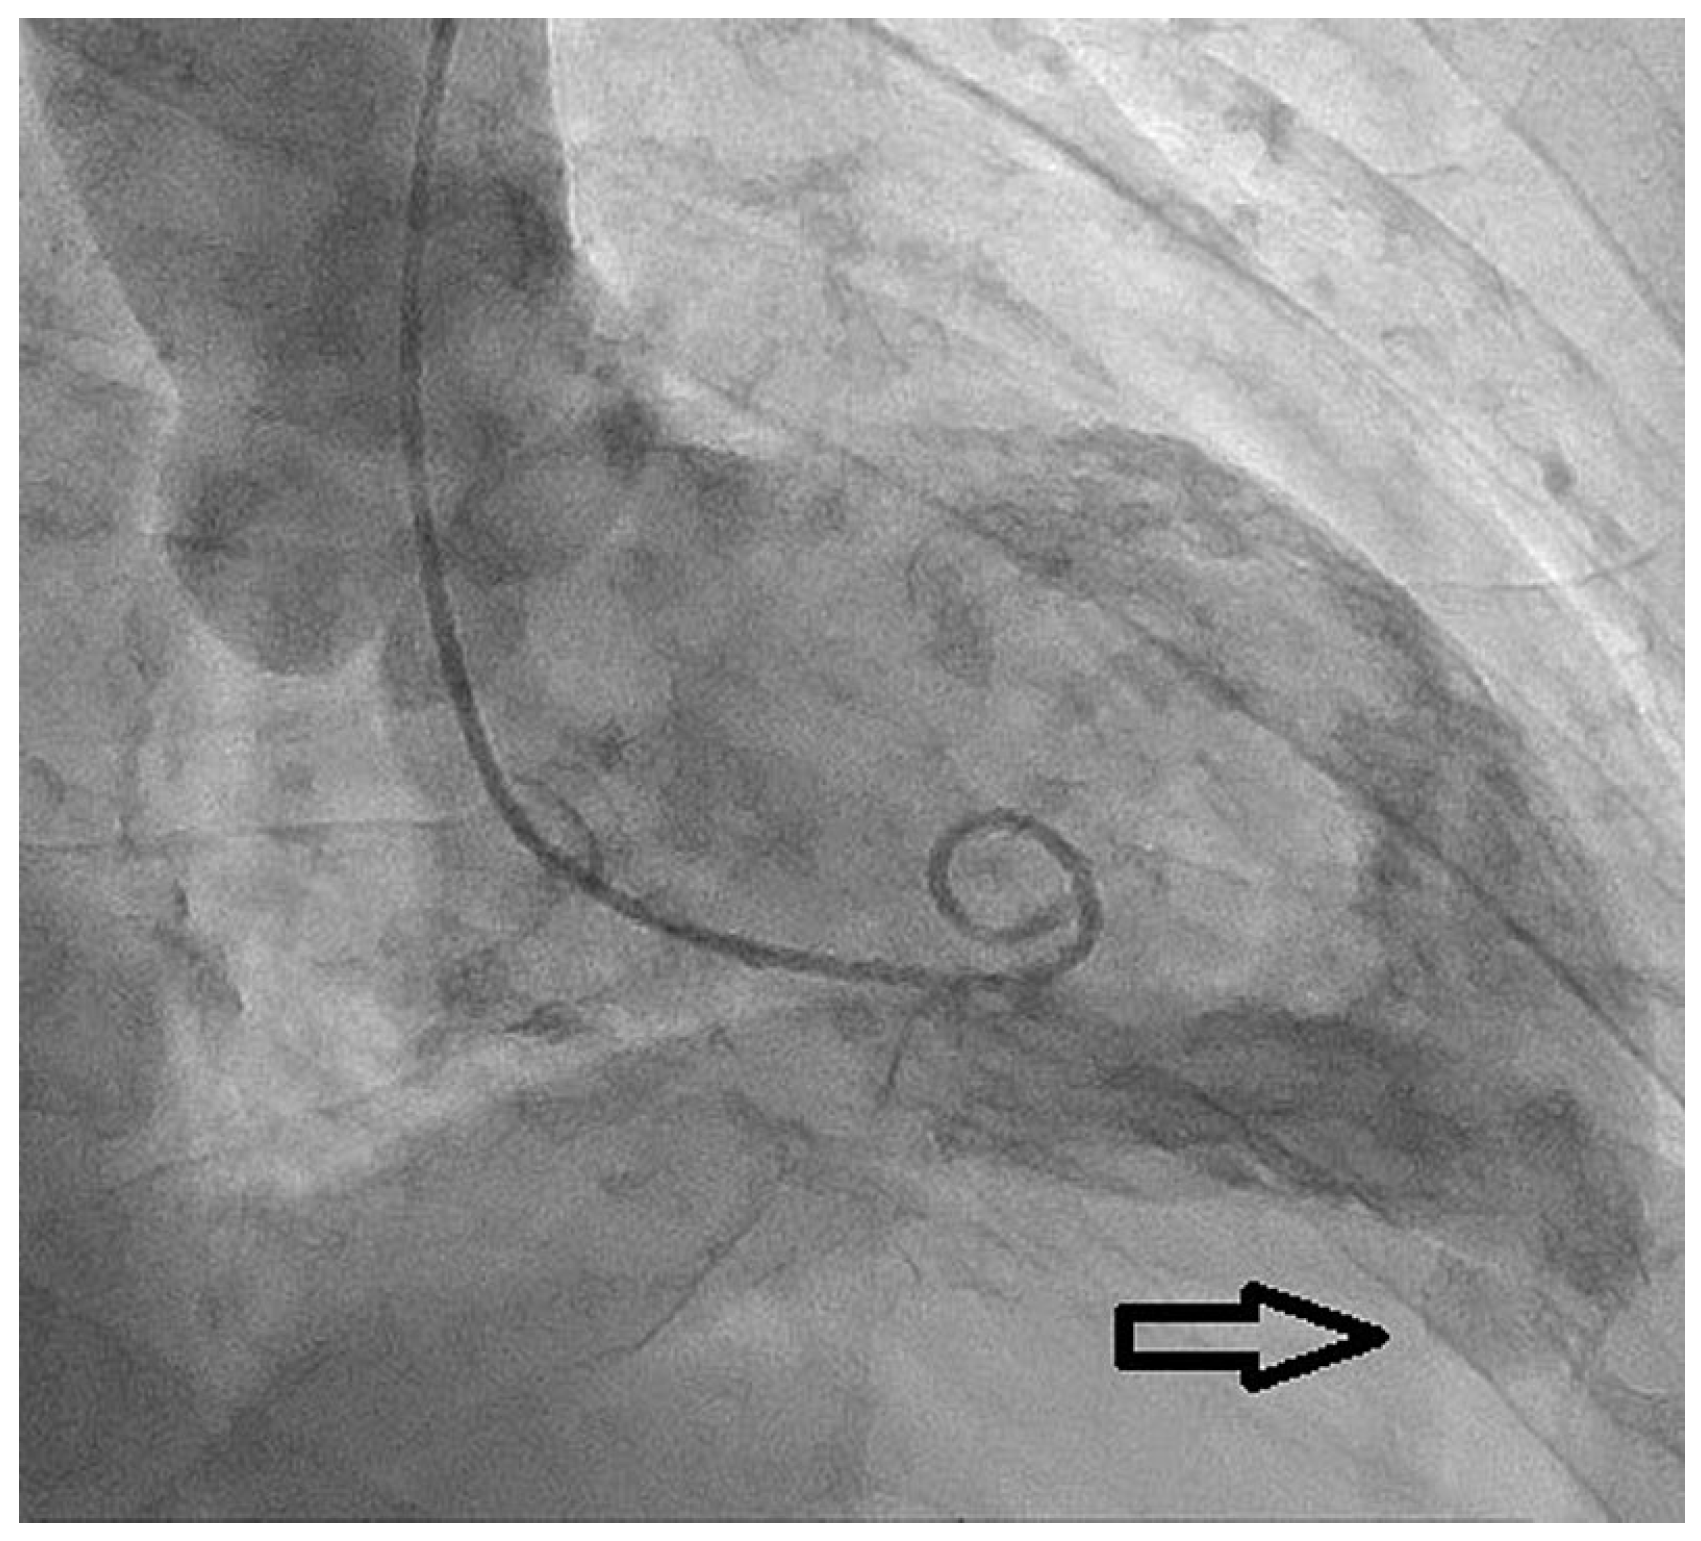

A 79-year-old male, with known ischaemic heart disease, was admitted to our emergency department because of acute abdominal pain and clinical suspicion of a ruptured abdominal aortic aneurism, which was confirmed by a computed tomography (CT) scan. His past history included hypercholesterolaemia treated with statins and silent myocardial ischaemia that was documented on prior myocardial scintigraphy. Emergent endovascular treatment of the aneurysm was successfully performed. The CT scan showed as an incidental finding the presence of a small left apical aneurysm (17 mm in its long axis and 7 mm at the base) (Figure 1).

Figure 3. Left ventriculogram: the examination showed the presence of a left ventricular apical diverticular excrescence (black arrow) without interventricular communication.

The coronary angiogram showed chronic total occlusion of the mid-right coronary artery, which was not treated as there was only slight ischaemia on scintigraphy and large epicardial collaterals from the left anterior descending artery (LAD). An intermediate lesion on the LAD was not haemodynamically significant after instantaneous wave-free ratio measurement (IFR 0.94). Left ventriculography confirmed the presence of an apical lesion compatible with a left ventricular diverticulum (Figure 3).